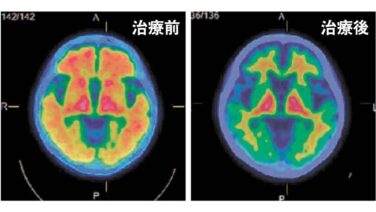

エッヂ うつ病の薬めっちゃ効いてる部